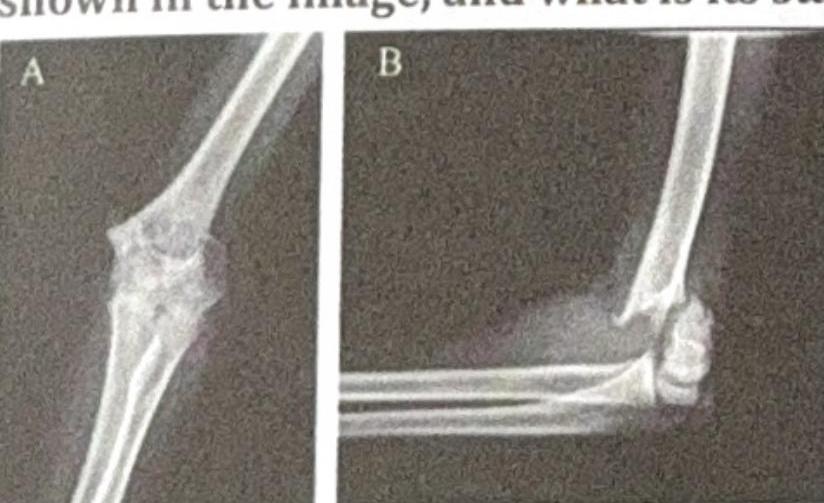

Explanation: ***Salter Harris 3*** - The image shows a **fracture extending from the epiphyseal surface down through the growth plate (physis) and exiting through the epiphysis** into the joint. This configuration is characteristic of a Salter-Harris type III fracture. - Salter-Harris Type III fractures disrupt the **articular cartilage** and can have a poorer prognosis due to potential joint incongruity and growth disturbance if not properly reduced. *Gartland 3* - The **Gartland classification** is specifically used for **supracondylar fractures of the humerus** in children, which is a different type of fracture involving the distal humerus metaphysis, not typically the growth plate itself in this manner. - Gartland type 3 refers to a **completely displaced supracondylar fracture** with no cortical contact, involving the metaphysis proximal to the growth plate. *Gartland 2* - **Gartland type 2** describes a **displaced supracondylar fracture** with an intact posterior cortex, also referring to a fracture of the distal humerus metaphysis, not a trans-growth plate fracture. - This classification is not applicable to the image which clearly depicts a fracture involving the epiphysis and physis. *Salter Harris 2* - A **Salter-Harris type II fracture** involves the **physis and extends into the metaphysis**, creating a triangular fragment known as the "Thurston Holland sign." - In the provided image, the fracture line clearly extends into the **epiphysis**, not just the metaphysis, distinguishing it from a Salter-Harris type II.

Explanation: **Type II** - **Type II Salter-Harris fractures** involve a fracture line that extends through the growth plate (physis) and then exits through the metaphysis, carrying a portion of the metaphysis with it. - This is the most common type of Salter-Harris fracture, characterized by the presence of a **metaphyseal fragment** attached to the epiphysis. *Type I* - **Type I Salter-Harris fractures** involve a complete separation of the epiphysis from the metaphysis through the physis, without any bone fracture. - There is no involvement of the metaphysis or epiphysis in the fracture line itself, making it difficult to detect on X-ray unless displacement is significant. *Type III* - **Type III Salter-Harris fractures** involve a fracture line that extends through the growth plate and then exits through the epiphysis, extending into the joint. - This type does not involve a metaphyseal fragment; instead, a portion of the **epiphysis is fractured**. *Type IV* - **Type IV Salter-Harris fractures** involve a fracture line that passes through the epiphysis, across the growth plate, and then through the metaphysis. - This type extends through all three components (epiphysis, physis, and metaphysis) as a single fracture line, but it does not specifically involve a detached metaphyseal fragment in the way Type II does.